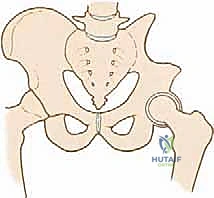

FIG 1 • The bony pelvis and its relation to the major blood vessels, nerves, and visceral organs.